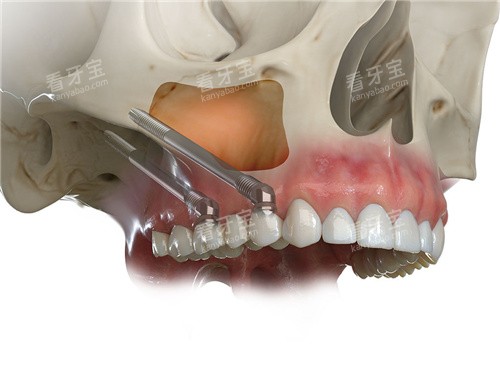

3.3 即刻负重:当天种牙当天用的秘密

(1)临时修复体的设计

术后立即安装预制的临时牙冠,其咬合接触面积需控制在天然牙的60%-70%,避免过度负荷。临时牙冠通过螺丝固位,便于后期调整。

无论是单颗牙缺失还是全口无牙颌,穿颧种植均可灵活应用。对于全口患者,可采用“All-on-4”穿颧方案,需要4-6颗种植体即可支撑整排牙冠,降低治疗成本。